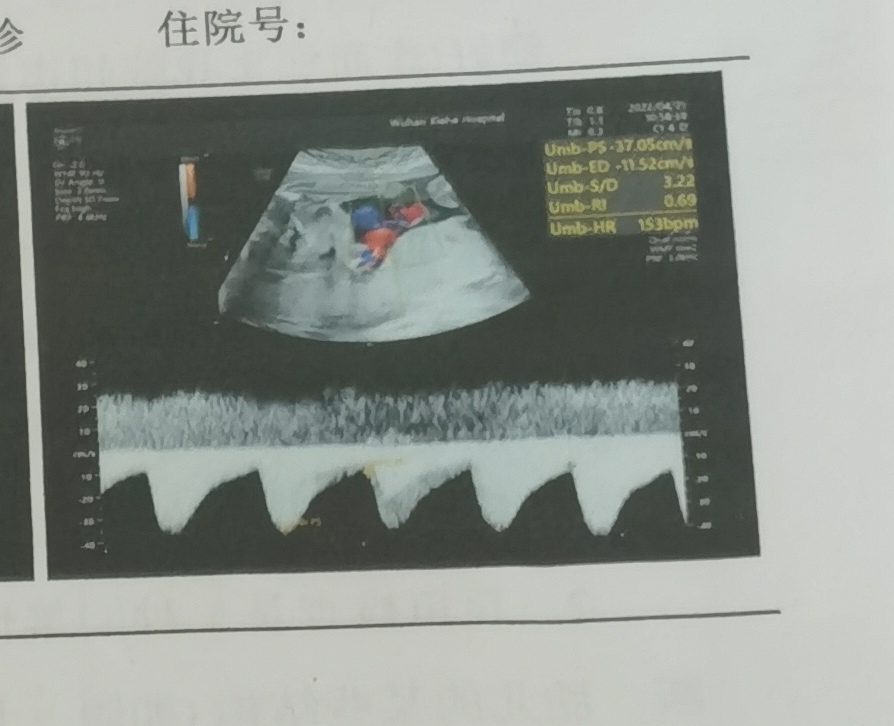

这个图是心脏吗?下面的是心脏波动吗?我看别人的上面波动没有这么大,我这个会不会不好。